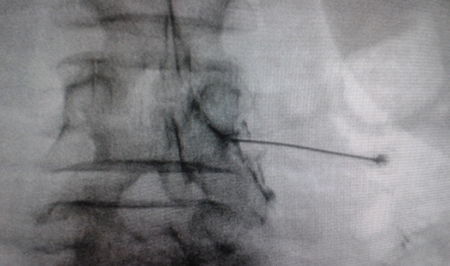

El acceso por vía transforaminal es el más utilizado (4). Se coloca al paciente en decúbito prono con una almohada a nivel abdominal para revertir la lordosis fisiológica. Las agujas o cánulas de radiofrecuencia que utilizamos con más frecuencia son de diámetro 20 o 22 G de 98 mm de largo con punta activa de 0,5 o 1 cm. Después de la asepsia con clorhexidina alcohólica y la colocación de campos estériles, se realizan enfoques radiológicos en incidencia anteroposterior, oblicuo y lateral. En incidencia anteroposterior y moviendo el arco en dirección cráneo caudal se borra el doble arco del borde inferior vertebral. En incidencia oblicua entre 20 y 30 grados ipsilateral al GRD a tratar, se visualizará la clásica imagen descrita como de “Scotty Dog”, que es resultado de acercar el macizo facetario y la apófisis espinosa al lado contralateral. El punto de entrada será entonces inmediatamente debajo del pedículo. Previa anestesia local con lidocaína al 1 %, la aguja se introducirá siguiendo una visión túnel y no se avanzará más allá de la mitad del pedículo en esta proyección con la finalidad de prevenir la lesión neural. En proyección lateral, se introducirá en el techo del neuroforamen

(Figuras 1 y 2) pero la localización final será determinada por la estimulación nerviosa sensitivo-motora. La estimulación sensitiva consiste en provocar parestesia o dolor en el territorio afectado con una estimulación entre 0,3-0,6 v. Durante la estimulación motora se pueden provocar fasciculaciones en el territorio afectado con un voltaje del doble al necesario para provocar las parestesias. Si se desea realizar una denervación intraganglionar, promulgada por algunos autores, la estimulación tanto sensorial como motora será positiva a menos de 0,3 v. Por tratarse de un procedimiento más doloroso, se aconseja administrar anestésicos locales después del estímulo doloroso y antes de realizar el tratamiento. La impedancia deberá mantenerse por debajo de 450 ohms, lo que se consigue infundiendo solución salina previa a la RF (4). La utilización de contraste constituye una buena práctica, ya que descarta la posición intravascular e intratecal de la cánula de radiofrecuencia.

Fig. 2. Imagen radiológica anteroposterior de una cánula de radiofrecuencia posicionada en neuroforamen L4-L5, en el llamado triángulo de seguridad, después de la inyección de contraste. Se observa un engrosamiento del radiculograma a nivel del techo del neuroforamen, que podría corresponder al ganglio de la raíz dorsal de L4